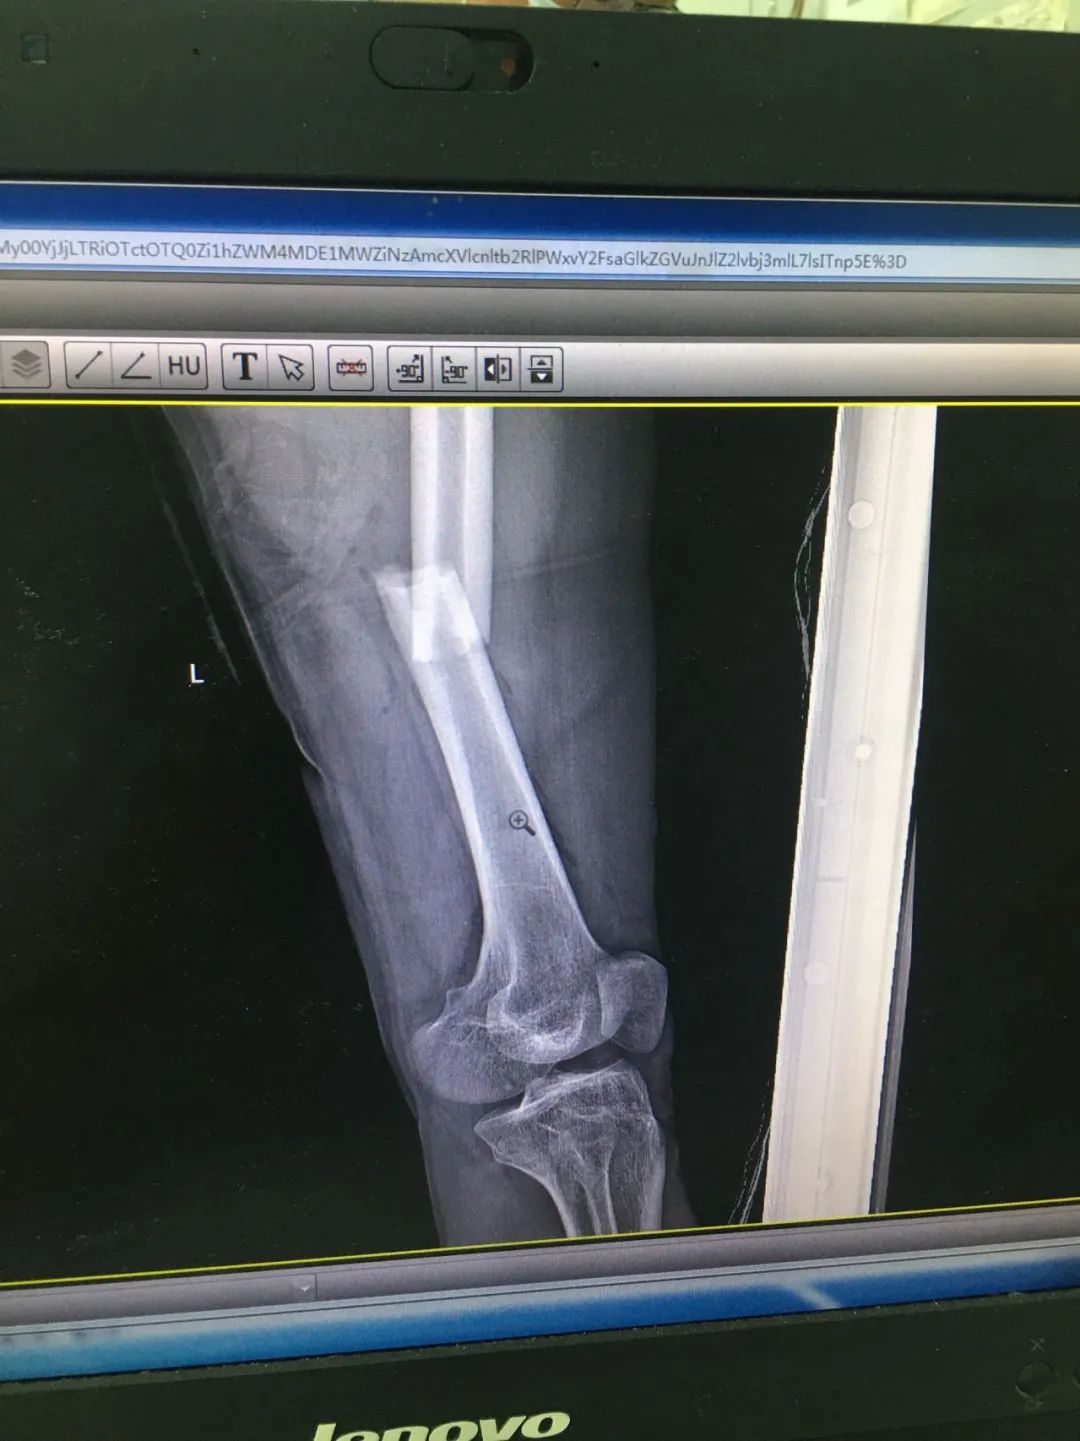

入院時,劉先生已失血性休克。急診科為劉先生安排X線及CT攝片檢查,顯示左股骨干、左腓骨上端骨折,左脛骨遠端粉碎性骨折,頭皮及全身多處皮膚軟組織挫裂傷,隨后收治于骨科。

第1次手術10天后,骨科為劉先生安排了第2次手術,歷經(jīng)3個小時,成功完成左股骨干骨折及左脛骨遠端骨折閉合復位內(nèi)固定術,植入兩根30cm×10mm、34cm×10mm髓內(nèi)釘。

術后一周,患者手術切口愈合良好,左下肢皮膚感覺及肌力正常,左足末梢循環(huán)恢復,復查X片顯示骨折復位標準,內(nèi)固定物位置良好。